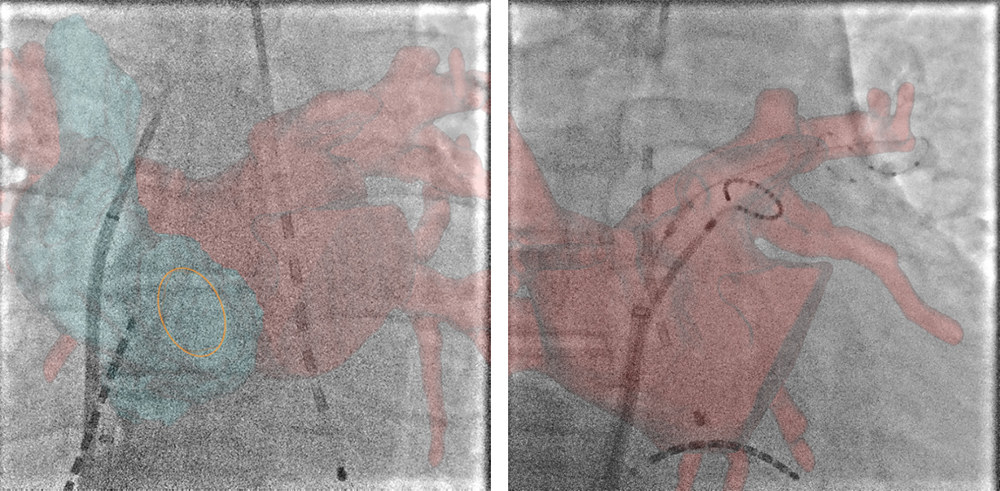

Innova Syncro3D

ワークステーションで作成したボリュームレンダリング(VR)画像とアームを同期連動する機能です。この機能にはVR画像を正面アームの角度に追従させて連動する機能とVR画像で決定した角度情報をアームに転送して連動させる機能があります。位置合わせを必要としないため簡便に利用できます。下図に使用例を提示します。術中に、「右冠動脈本幹と右室枝を分離できる角度を探してほしい」との依頼があり、VR画像上で右冠動脈本幹と右室枝の短軸にワイヤーフレームを表示させ、2つのワイヤーフレームが直線になる角度、すなわち分離の良い角度を確認した後、この角度をInnova Syncro 3D機能によって正面アームに連動させました。連動時のアーム挙動は、転送した角度に近い側のアームがポジション移動し、対側アームは直行する角度へポジション移動されます。

IGS620_kurume_07.jpg

VR画像で右冠動脈本幹と右室枝の短軸が分離できる角度を確認し、Cアームに角度情報を連動させた(RAO 45度、CRA 17度)